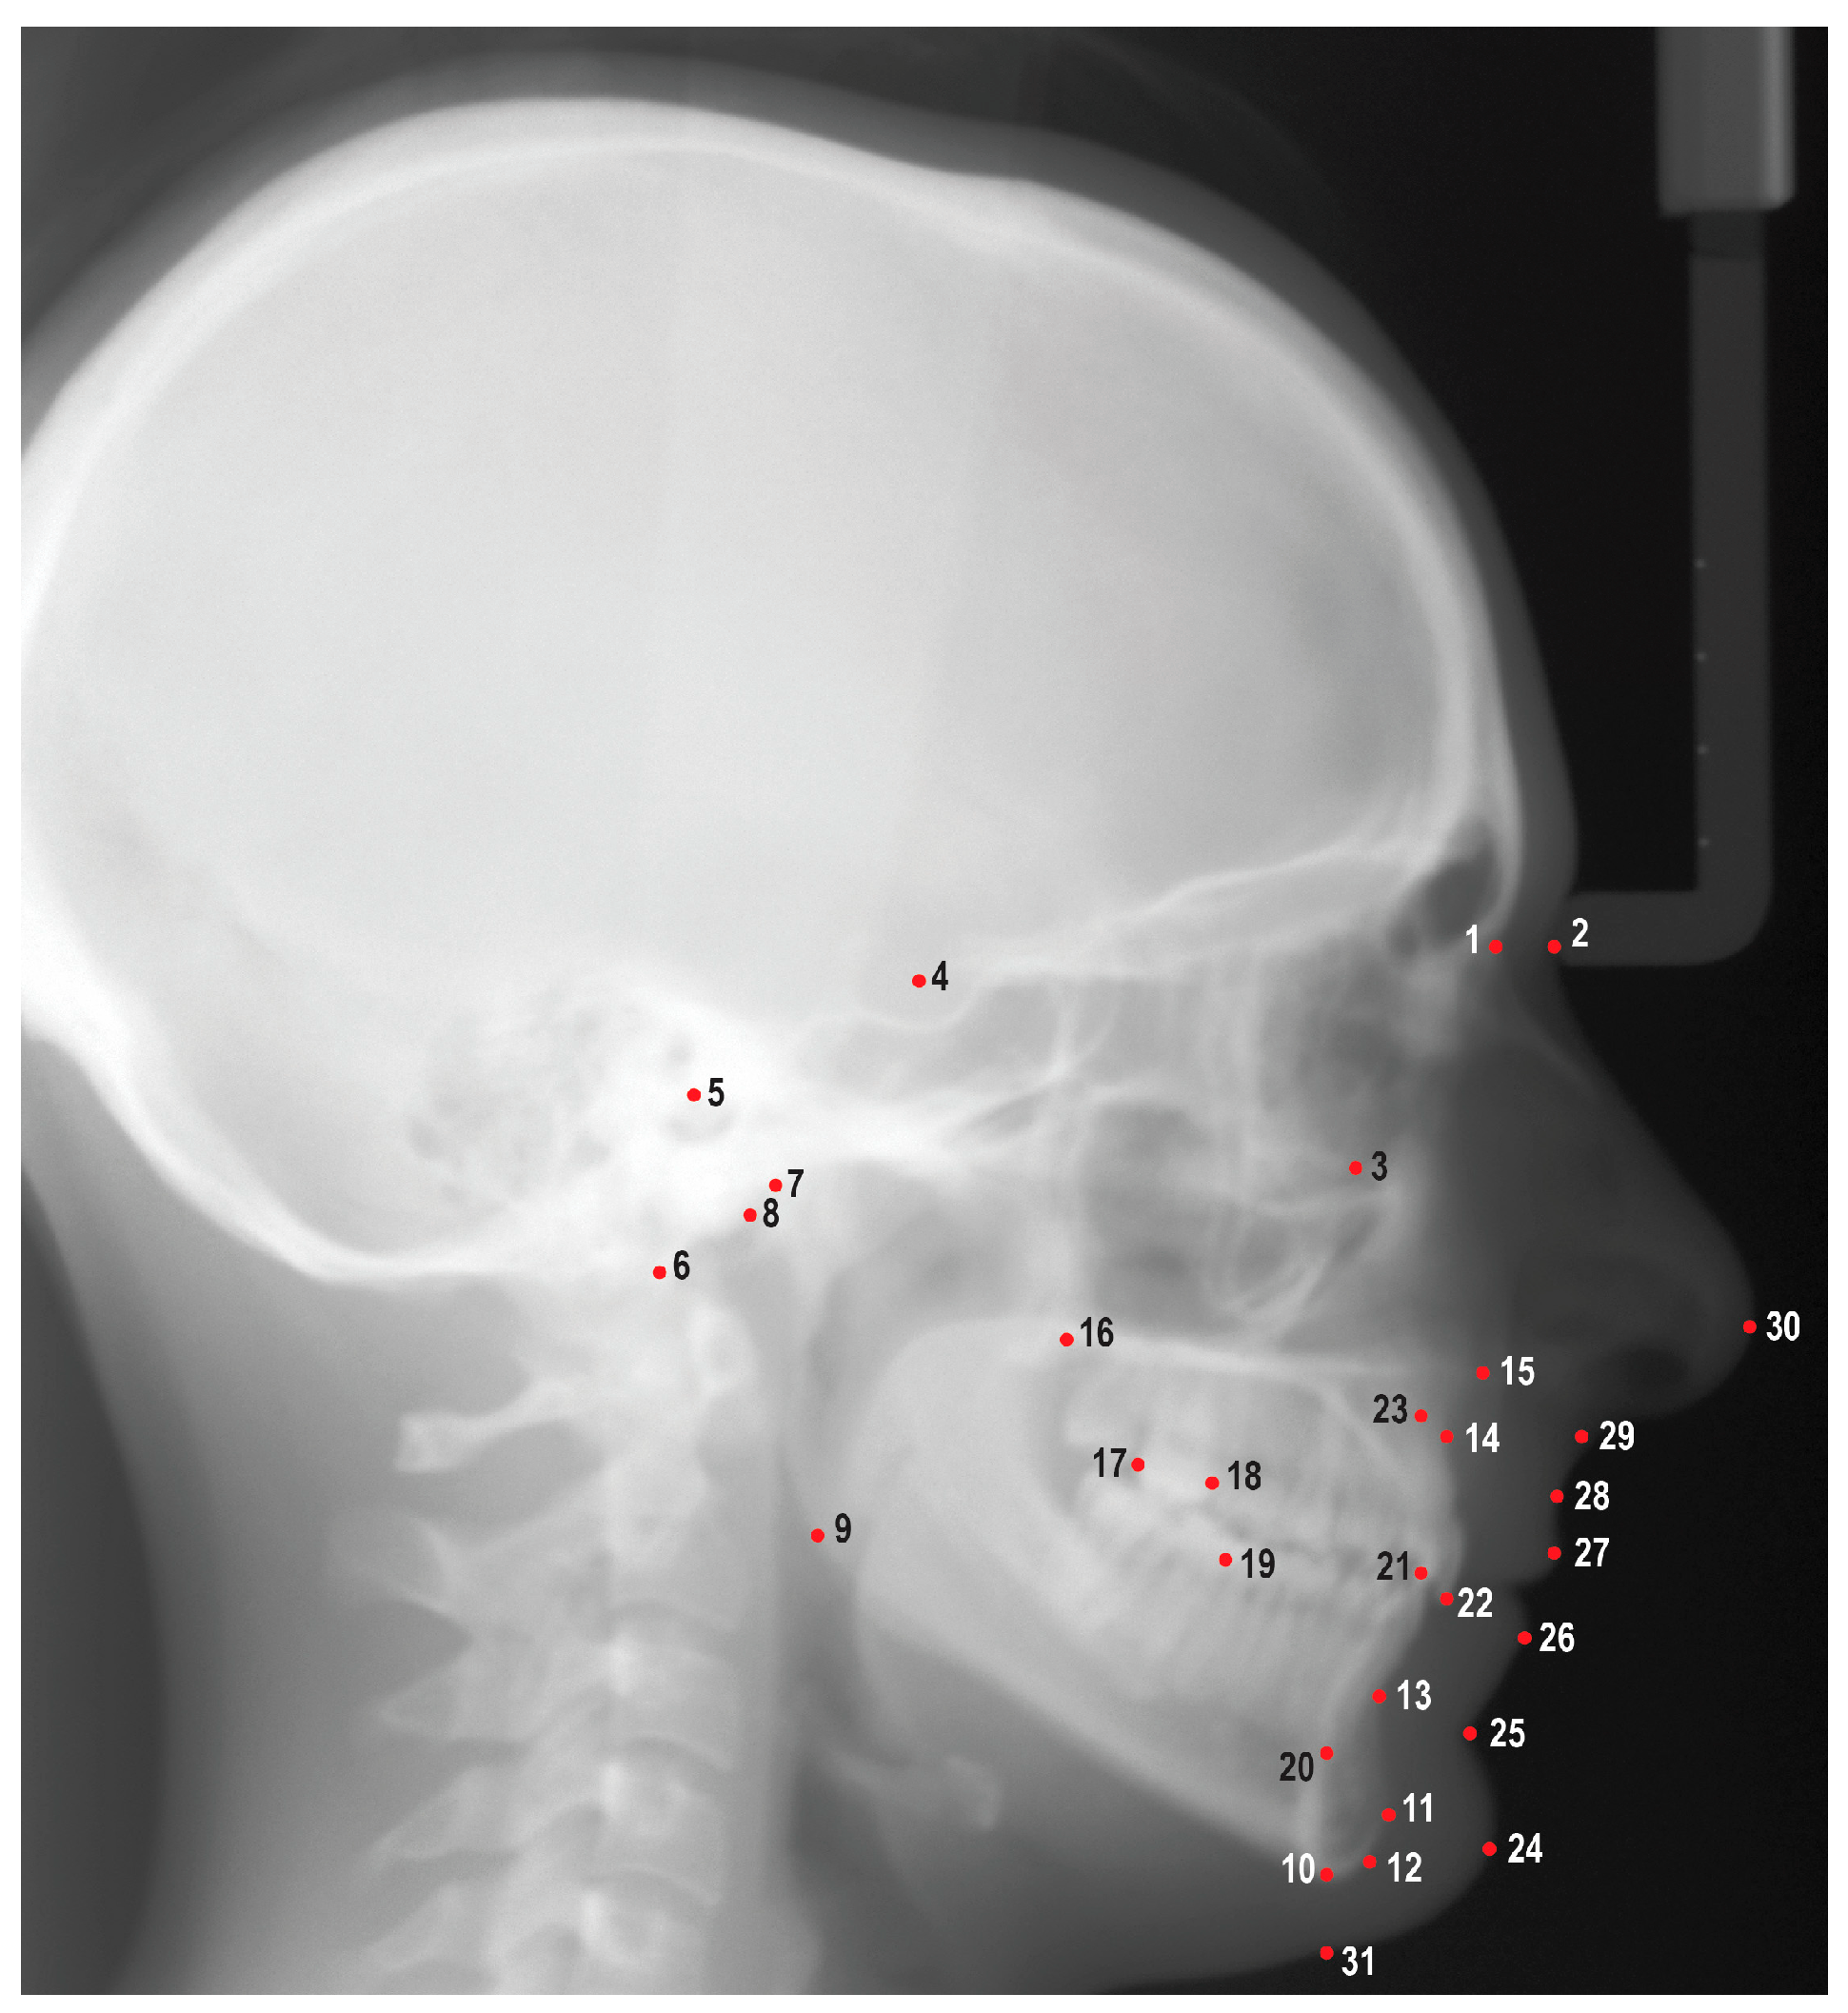

| Category | Measurements | Definitions |

|---|---|---|

| Maxilla to Cranial Base | SNA (°) | The angle formed by connecting the sella, nasion, and A point. |

| SN-Palatal Plane (°) | The angle formed from the intersection of the sella-nasion line and a line drawn connecting the anterior nasal spine to the posterior nasal spine. | |

| SN-Occlusal Plane (°) | The angle formed from the sella-nasion and occlusal plane. | |

| A-N Perpendicular (mm) | The linear distance from A point to the nasion perpendicular. | |

| Mandible to Cranial Base | SNB (°) | The angle formed by connecting the sella, nasion, and B point. |

| SNPg (°) | The angle formed by connecting the sella, naison, and pogonion. | |

| FMA: MP-FH (°) | The angle formed from the intersection of the porion-orbitale line and a line drawn connecting the gonion to the gnathion. | |

| SN-MP (°) | The angle formed from the intersection of the sella-nasion line and a line drawn connecting the gonion to the gnathion. | |

| Mandibular Plane to Occlusal Plane (°) | The angle formed by the mandibular plane and the occlusal plane. | |

| B-N Perpendicular (mm) | The linear distance from the B point to the nasion perpendicular. | |

| Pog-N Perpendicular (mm) | The linear distance from the pogonion to the nasion perpendicular. | |

| Y-Axis: SGn-SN (°) | The angle formed by connecting the nasion, sella, and gnathion. | |

| Maxilla to Mandible | ANB (°) | The difference between SNA and SNB. |

| Palatal-Mandibular Angle (PP-MP) (°) | The angle formed from the palatal plane and the mandibular plane. | |

| Wits Appraisal (mm) | The distance between A point to the occlusal plane and B point to the occlusal plane. | |

| Maxillary Length: ANS-PNS (mm) | The linear measurement between the anterior nasal spine and the posterior nasal spine. | |

| Mandibular Length: Co-Gn (mm) | The linear measurement between the condylion and the gnathion. | |

| Cranial Base | Cranial Base Flexure Angle: Ba-S-N (°) | The angle formed by connecting the basion, sella, and nasion. |

| Upper Incisors to Maxilla | U1-SN (°) | The angle formed by a line connecting the sella and the nasion and a line connecting the upper incisor incisal tip to the root apex. |

| U1-NA (°) | The angle formed by a line connecting the nasion to the A point and a line connecting the upper incisor incisal tip to the root apex. | |

| U1-NA (mm) | The linear measurement from the labial surface of the upper incisor to the line connecting the nasion to the A point. | |

| U1-Palatal Plane (°) | The angle formed by the position of the maxillary incisor to the palatal plane. | |

| U1 Protrusion (U1-APo) (mm) | The distance from the maxillary incisor to the A point-pogonion reference line. | |

| Lower Incisors to Mandible | L1-MP (°) | The angle formed by a line connecting the lower incisor incisal tip to the root apex and a line connecting the gonion to the gnathion. |

| L1-NB (°) | The angle formed by a line connecting the lower incisor incisal tip to the root apex and a line connecting the nasion to the B point. | |

| L1-NB (mm) | The linear measurement from the labial surface of the lower incisor incisal to the line connecting the nasion to the B point. | |

| L1 Protrusion (L1-Apo) (mm) | The distance from the mandibular incisor to the A point-pogonion reference line. | |

| Incisors to Each Other | Interincisal Angle (°) | The angle formed by a line connecting the lower incisor incisal tip to the apex and a line connecting the upper incisor incisal tip to the root apex. |

| Overjet (mm) | The horizontal distance from maxillary incisor tip to mandibular incisor tip. | |

| Overbite (mm) | The vertical distance from the maxillary incisor tip to the mandibular incisor tip. | |

| Soft Tissue | Upper Lip to E-Plane (mm) | The linear distance from the upper lip to a line connecting the soft tissue pogonion and pronasale. |

| Lower Lip to E-Plane (mm) | The linear distance from the lower lip to a line connecting the soft tissue pogonion and pronasale. | |

| ILG (HP) (mm) | The vertical distance from stomion superius to stomion inferius. | |

| Nasolabial Angle (Pn-Sn-UL) (°) | The angle formed by the pronasale, subnasale, and upper lip. | |

| H-Angle (Pg’UL-Pg’Na’) (°) | The angle formed by soft tissue pogonion-upper lip to soft tissue pogonion-soft tissue nasion. | |

| Facial Height (Na’-Me’) (mm) | The linear measurement from soft tissue nasion and soft tissue menton. | |

| Soft Tissue Upper Face Height: G’-Sn’ (mm) | The linear measurement between soft tissue glabella and soft tissue subnasale. | |

| Soft Tissue Lower Face Height: Sn’-Me’ (mm) | The linear measurement between soft tissue subnasale and soft tissue pogonion. | |

| Hard Tissue Upper Face Height: N-ANS (mm) | The linear measurement between the nasion and anterior nasal spine. | |

| Hard Tissue Lower Face Height: ANS-Me (mm) | The linear measurement between the anterior nasal spine and menton. | |

| UFH (N-ANS/(N-ANS + ANS-Me)) (%) | The ratio of the upper face height to facial height. | |

| LFH (ANS-Me/(N-ANS + ANS-Me)) (%) | The ratio of lower face height to facial height. | |

| Posterior Face Height: Ar-Go (mm) | The linear measurement between articulare and gonion. | |

| PFH:AFH (Co-Go:N-Me) (%) | The ratio of posterior facial height to anterior facial height. | |

| Profile | Convexity: NA-APo (°) | The angle formed by connecting the nasion, A point, and pogonion. |

| Facial Angle: FH-NPo (°) | The angle formed by a line connecting the porion to the orbitale and a line connecting the nasion to the pogonion. |